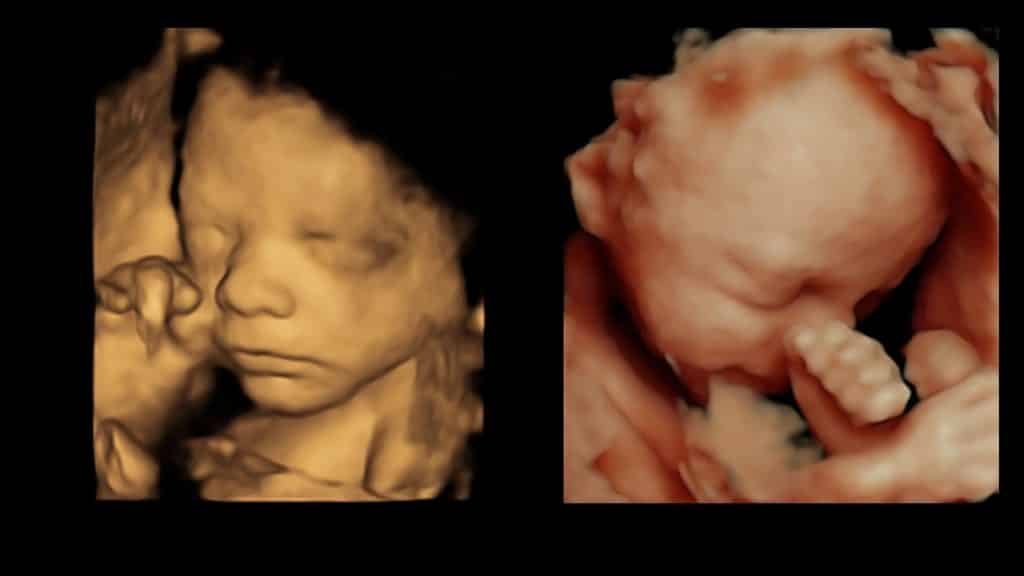

A 3D scan captures a detailed, still image of your baby, while a 4D scan brings those moments to life with moving images. For an even more enhanced experience, our HDlive scan utilises the latest in ultrasound technology to provide you with an incredibly clear and realistic view of your little one.

Below is a comparison between 4D & HDlive: